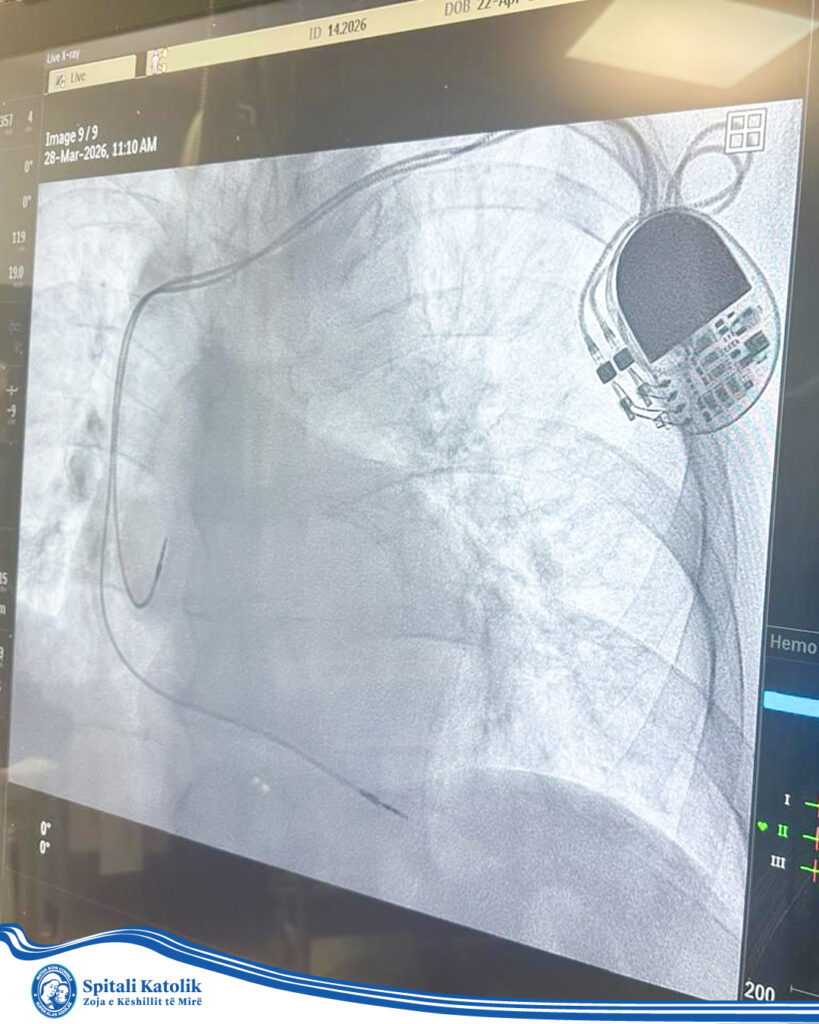

Procedurat e vendosjes së pacemaker pranë Spitalit Katolik Zoja e Këshillit të Mirë kryhen nga mjekë me përvojë evropiane, duke garantuar siguri dhe kujdes maksimal për çdo pacient.

Pacemaker-i është një pajisje e vogël mjekësore që vendoset në kraharor për të ndihmuar zemrën të rrahë në ritëm normal. Përdoret kryesisht tek pacientë që kanë probleme me ritmin e zemrës .

- Vendoset me një procedurë relativisht të thjeshtë kirurgjikale